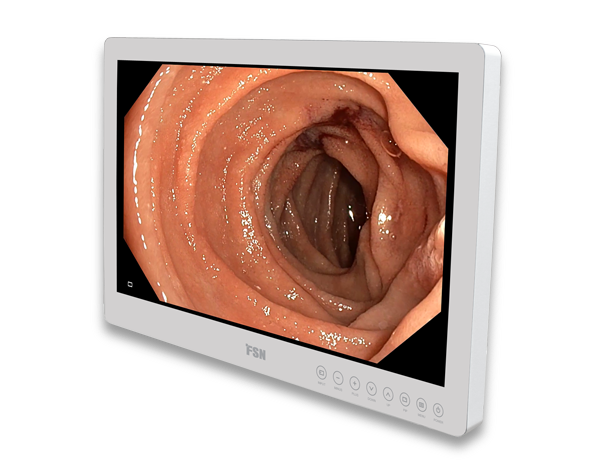

LED COLD LIGHT SOURCE

LED COLD LIGHT SOURCE

LED COLD LIGHT SOURCE

LED COLD LIGHT SOURCE

HD MEDICAL MONITOR

HD MEDICAL MONITOR

Sino scope 0°-2.7mm-175mm

Sino scope 0°-2.7mm-175mm

Laryngoscope 70°-6mm-184mm

Laryngoscope 70°-6mm-184mm

Huger Endoscopy system Refurbished

Huger Endoscopy system Refurbished

Intra Oral Camera With Screen

Intra Oral Camera With Screen

ENT diagnostic Endoscpe INV250

ENT diagnostic Endoscpe INV250